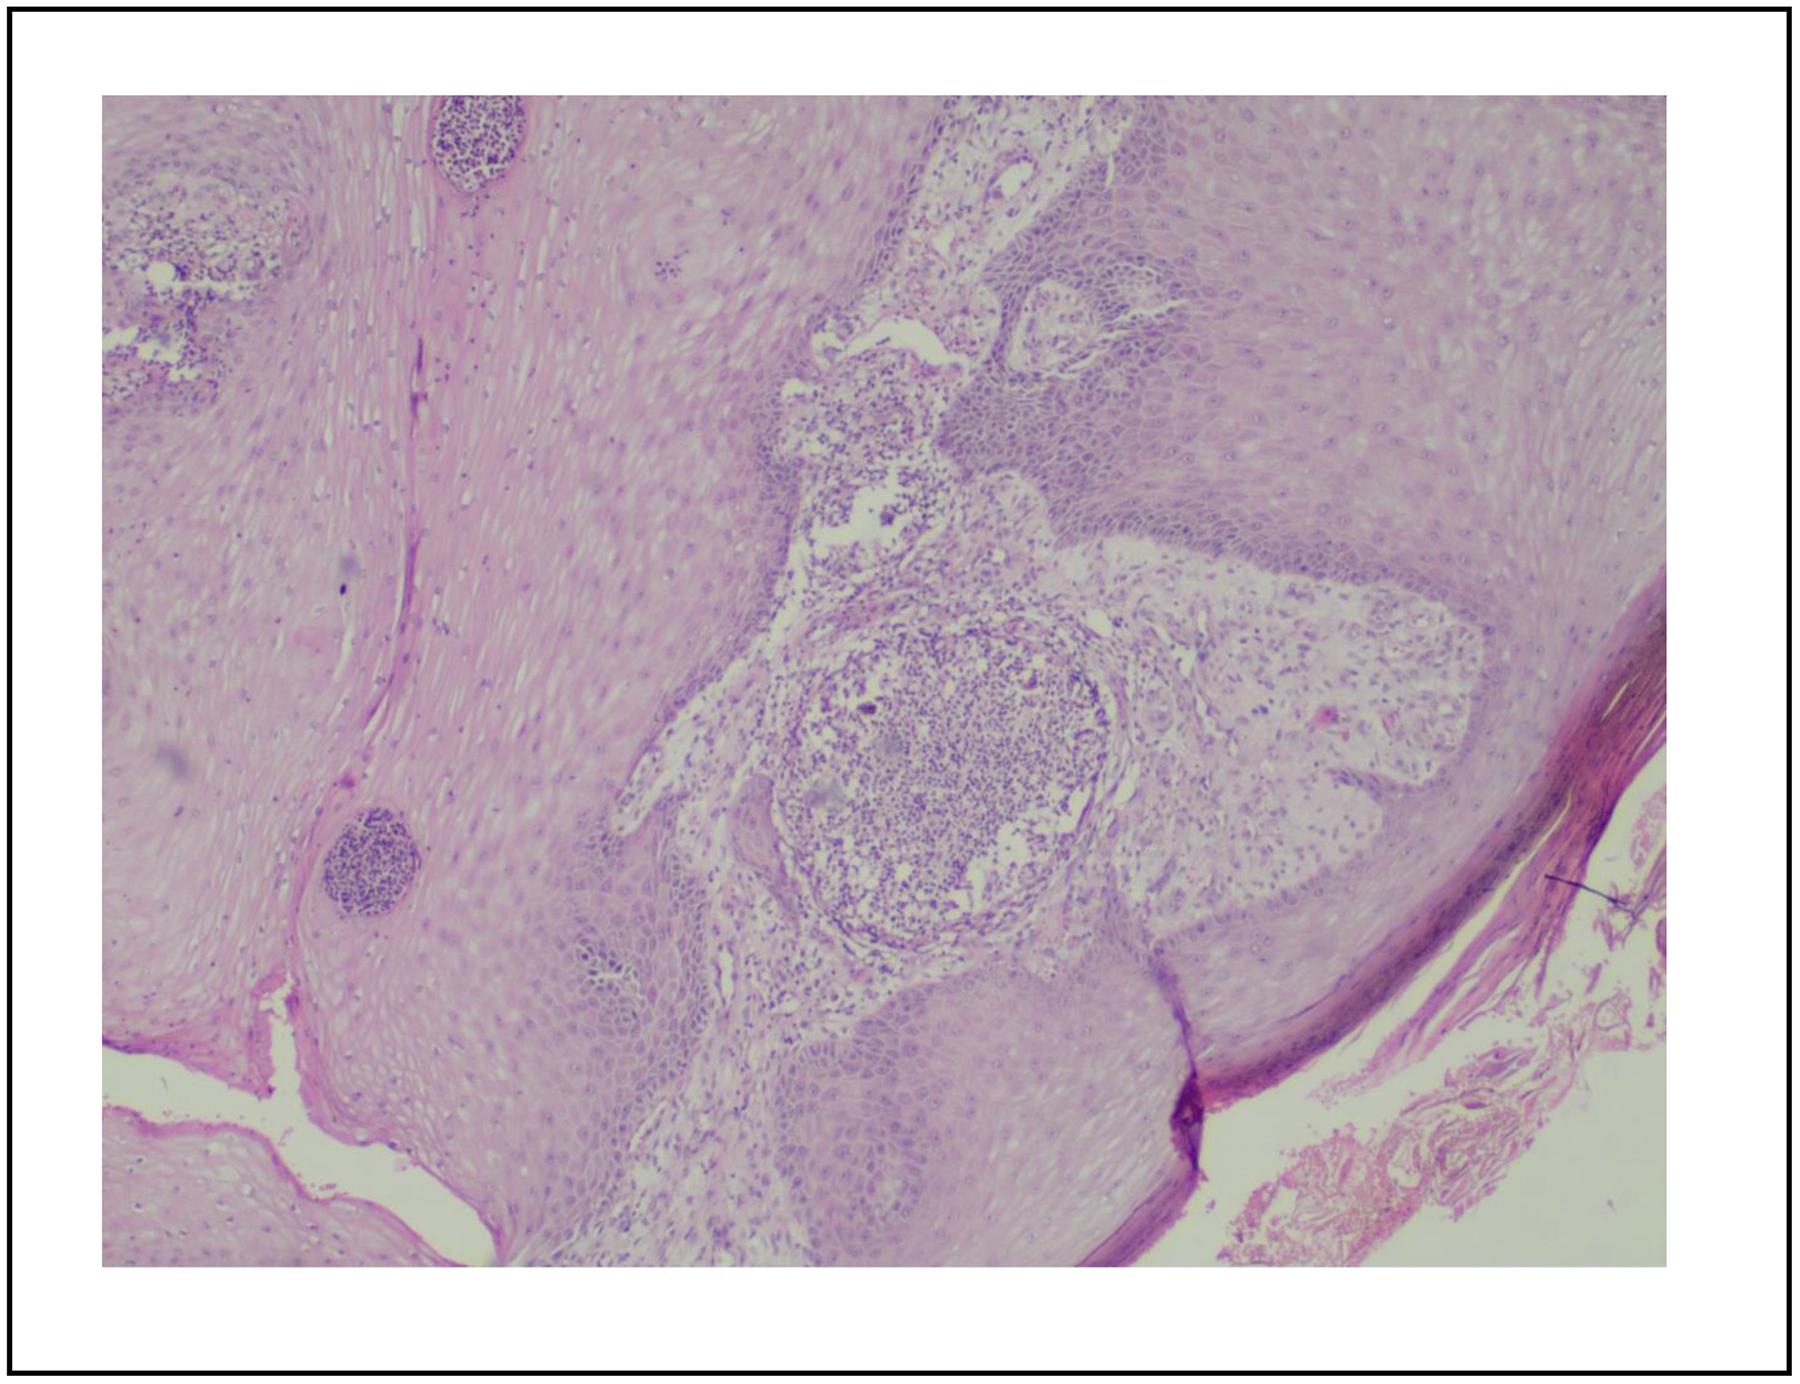

El paciente acudió a los 30 días al servicio de dermatología, quien reviso los reportes: El KOH reveló estructuras micóticas y presencia de levaduras en muestras de brazo y pie izquierdo. El aislamiento microbiológico reportó crecimiento de Fonsecaea spp. La biopsia de piel de dorso de pie izquierdo evidenció cuerpos escleróticos pigmentados conocidos como cuerpos de Medlar patognomónicos de CBM (Figura 2), además mostró hiperplasia pseudoepiteliomatosa con abscesos intraepidérmicos y los cuerpos escleróticos fúngicos pigmentados (Figura 3).

Figura 3. Hiperplasia pseudoepiteliomatosa, y abscesos intraepidérmicos con cuerpos de Medlar.